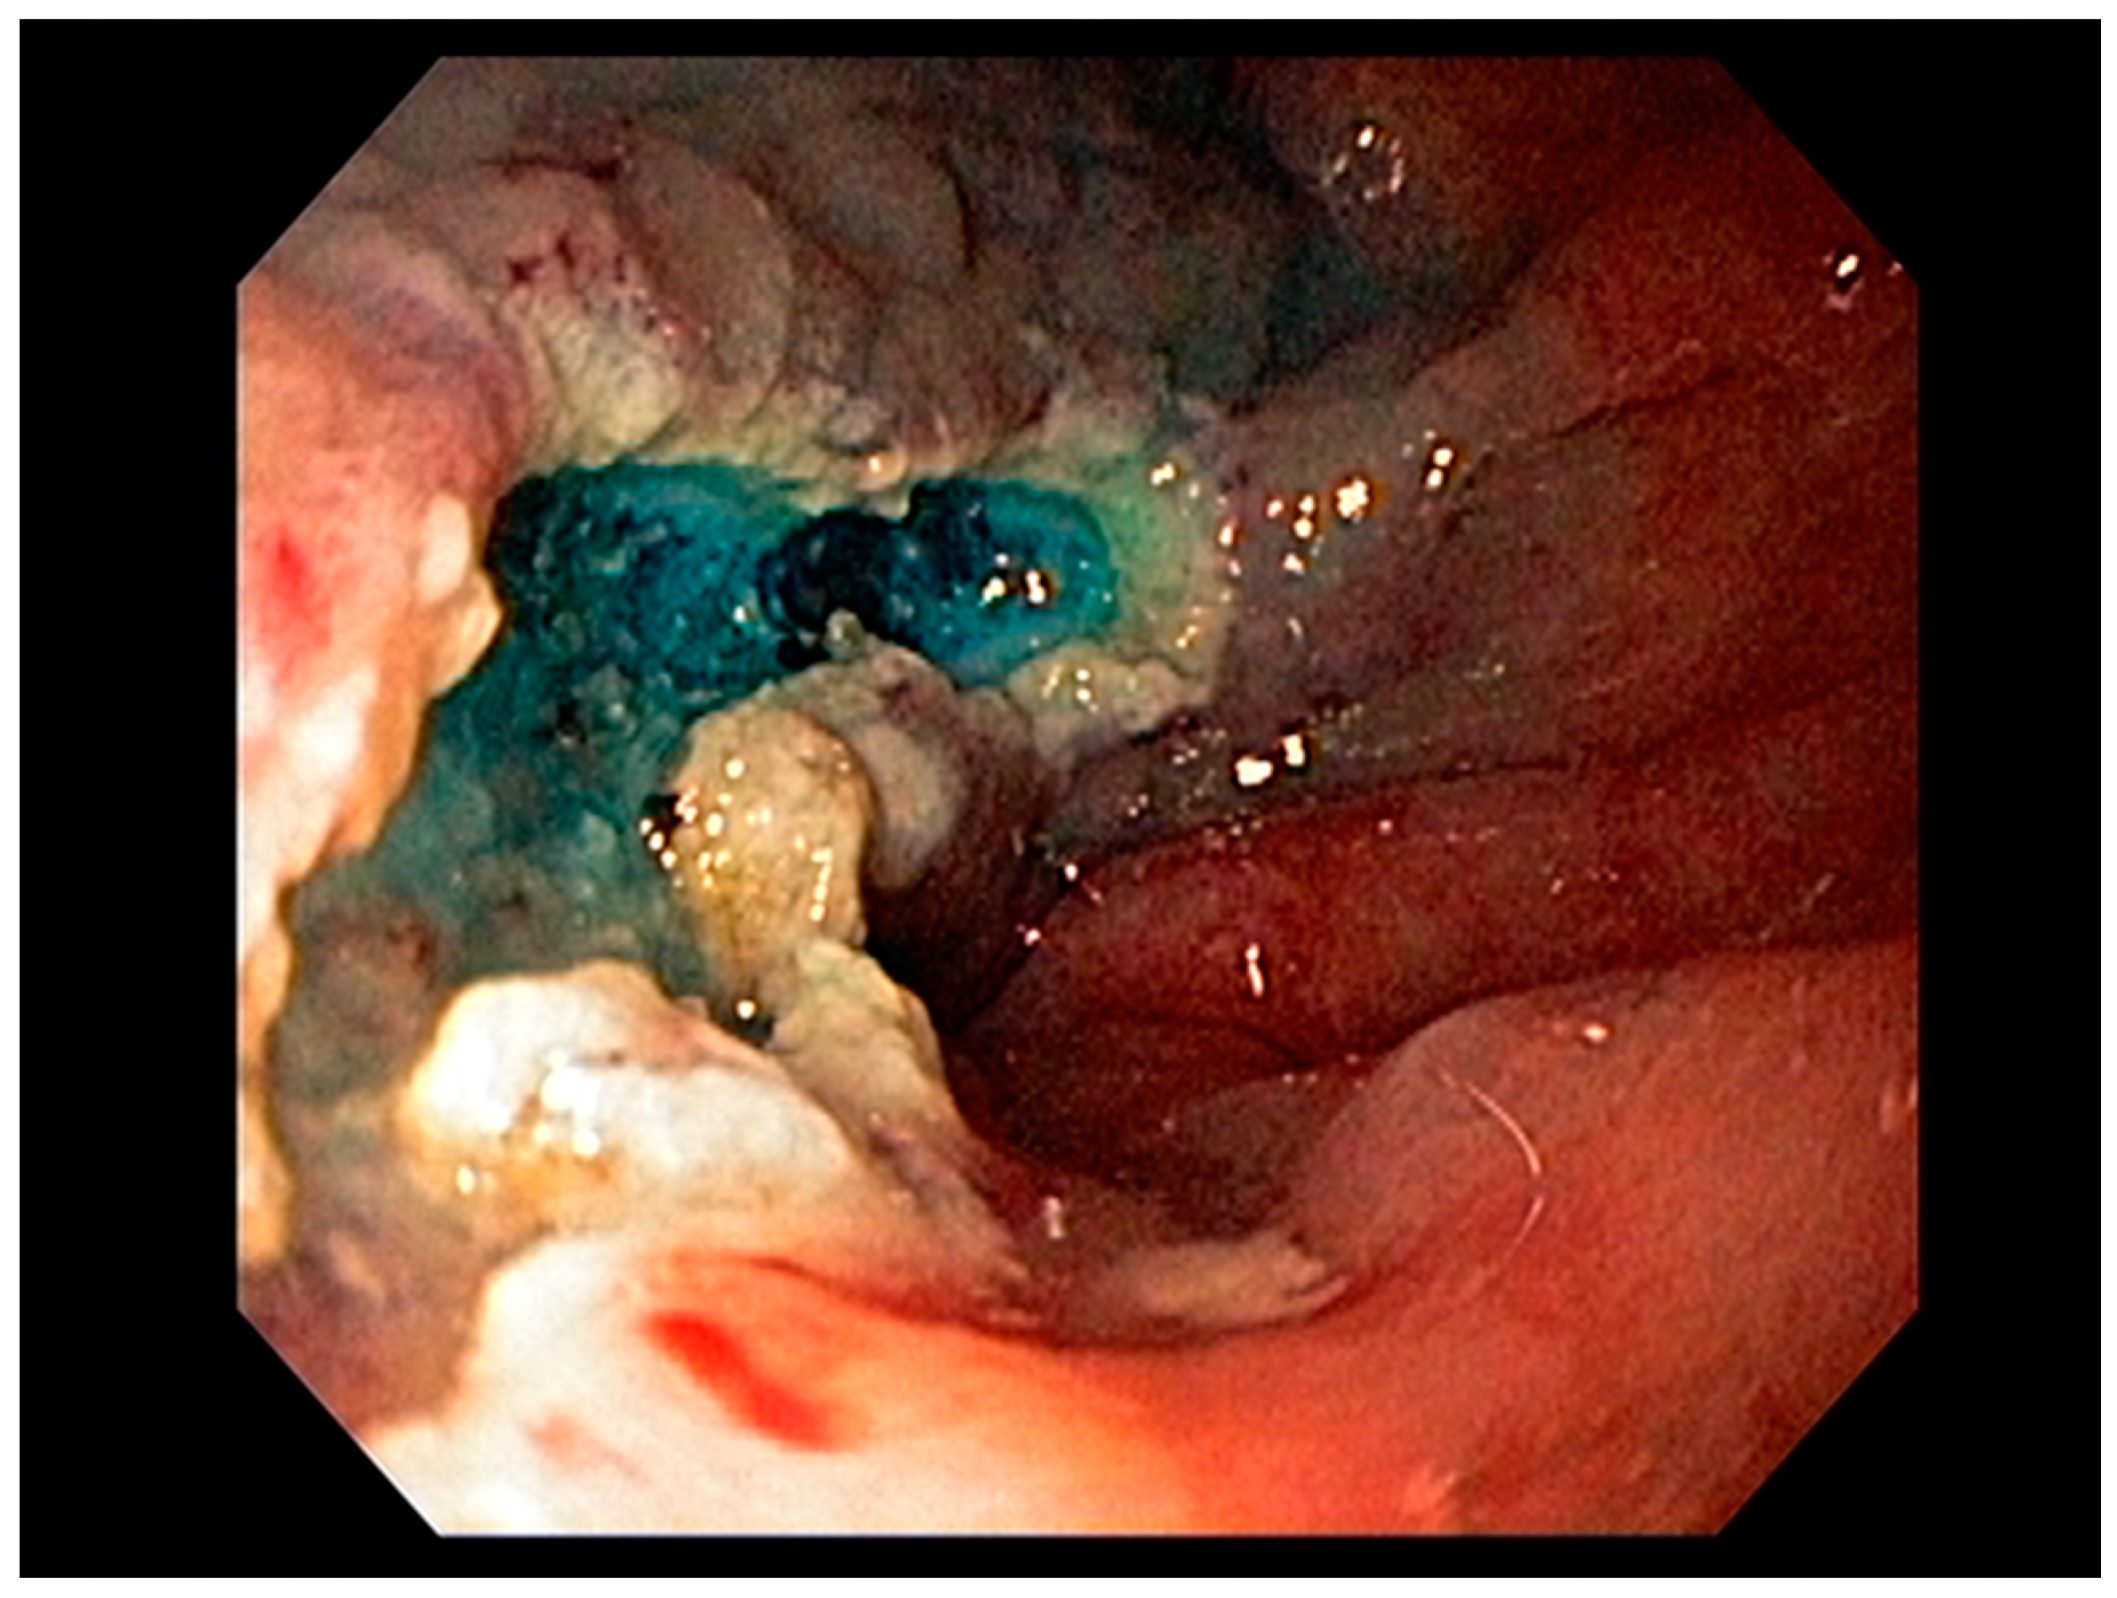

3.1. Endoscopic Therapeutic Options for Barrett’s Esophagus Associated Dysplasia

3.2. Endoscopic Resection Techniques for Early-Stage Esophageal Cancer (T1a and T1b)

4.3. Endoscopic Ultrasound in Staging of Gastric Cancer